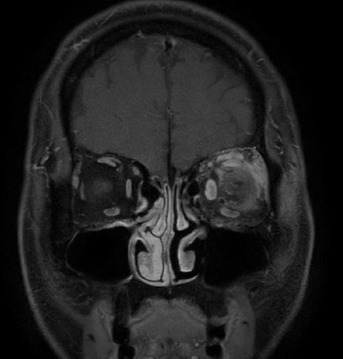

进行Alcian蓝和促甲状腺激素染色,发现黏蛋白沉积,促甲状腺激素呈阴性。组织病理学表现提示眼部黏蛋白增多症。根据临床和组织学表现,诊断为甲状腺眼病,甲状腺功能检测显示亚临床甲亢,眼部磁共振成像

显示左侧眼外肌和组织增厚。

图1 眼部磁共振成像结果

5名患者的临床特征见表1。其中4名患者接受了Alcian蓝和促甲状腺激素染色的眼睑皮肤活检。所有5名患者均出现眼睑肿胀,其中1名伴有瘙痒。病例1患者伴有眼球突出

、眶周肿胀和眼球运动受限,接受了眼部磁共振成像,证实眼外肌肉和软组织肿胀。上眼睑组织病理学检查显示,所有患者均伴有真皮胶原纤维间的黏蛋白沉积以及淋巴细胞浸润,但不影响表皮。病例4患者经促甲状腺激素染色活检显示促甲状腺激素受体的过度表达。5名患者中有4名甲状腺功能检查结果为正常,另外1名为亚临床甲亢。此外,病例5患者伴有TPO阳性,甲状腺功能正常。